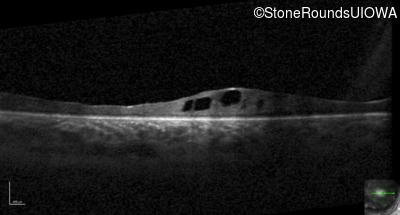

Optical Coherence Tomography - Right - 20/500

Exemplar / OCT Stack

OCT Stack